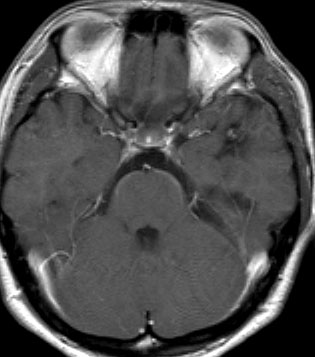

腫瘍から少し出血したために,患者さんはけいれん(てんかん発作)を起こしました。左のT1強調画像では出血を疑います。中央のT2強調画像では海綿状血管腫の周りに脳浮腫があるために白くぼやけた部分があります。右の造影剤を使ったMRIでは造影剤が入るところがほどんど無いことがわかります。側頭葉の海綿状血管腫は側頭葉てんかんという症状で発症することが多いです。

出血が溶けて少し小さくなっています。海綿状血管腫の周りには黒い縁取りがあります。この黒い部分は血液が溶けて残った鉄が脳の中にたまったことを示しています(siderosisといいます)。この鉄のしみ込みはけいれんの原因になると考えられます。この海綿状血管腫は中等度の大きさですが,治療が難しいほどのてんかんが無ければ手術などしないでほっておいてもいいです。手術で側頭葉(特に海馬)を損傷すると記憶の障害などもでます。